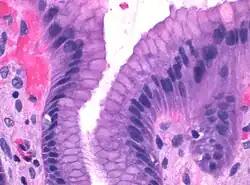

Foveolacellen of oppervlakteslijmcellen zijn slijmproducerende cellen die de binnenkant van de maag bedekken en beschermen tegen de corrosieve werking van maagzuur. De foveolacellen hebben alle een klierfunctie gekregen en zijn van het mukeuze type. Ze hebben een helder cytoplasma. De foveolacellen bekleden het maagslijmvlies en de maagholtes. Ze vormen een eenlaags cilindrisch epitheel.

Het maagslijmvlies dat de binnenwand van de maag bekleedt, heeft een reeks microscopische structuren, maagklieren genaamd, die, afhankelijk van hun locatie in de maag, verschillende stoffen afscheiden in het lumen van het orgaan. De openingen van deze klieren in de maag worden foveolae (maaggroefjes) genoemd, die bekleed zijn met foveolacellen om een beschermende alkalische afscheiding te vormen tegen het corrosieve maagzuur.[2]

Foveolacellen hebben grote hoeveelheden mucinekorrels in hun apicale (bovenste) oppervlak en hebben korte microvilli, die uitsteken in het lumen van de maag.[2] Mucinen zijn grote glycoproteïnen die het slijm zijn gelachtige eigenschappen geven.[3] Mucinen kleuren de cellen sterk met speciale kleuringstechnieken zoals PAS-reactie of toloniumchloride; de laatste staat symbool voor de anionische aard van foveolacelsecreties. Onder de mucinekorrels zitten een golgicomplex, de celkern en kleine hoeveelheden ruw endoplasmatisch reticulum.[4] De slijmhalscellen in de maagklieren zijn korter dan de foveolacellen en bevatten in hun apicale oppervlak kleinere hoeveelheden mucinekorrels.[4]